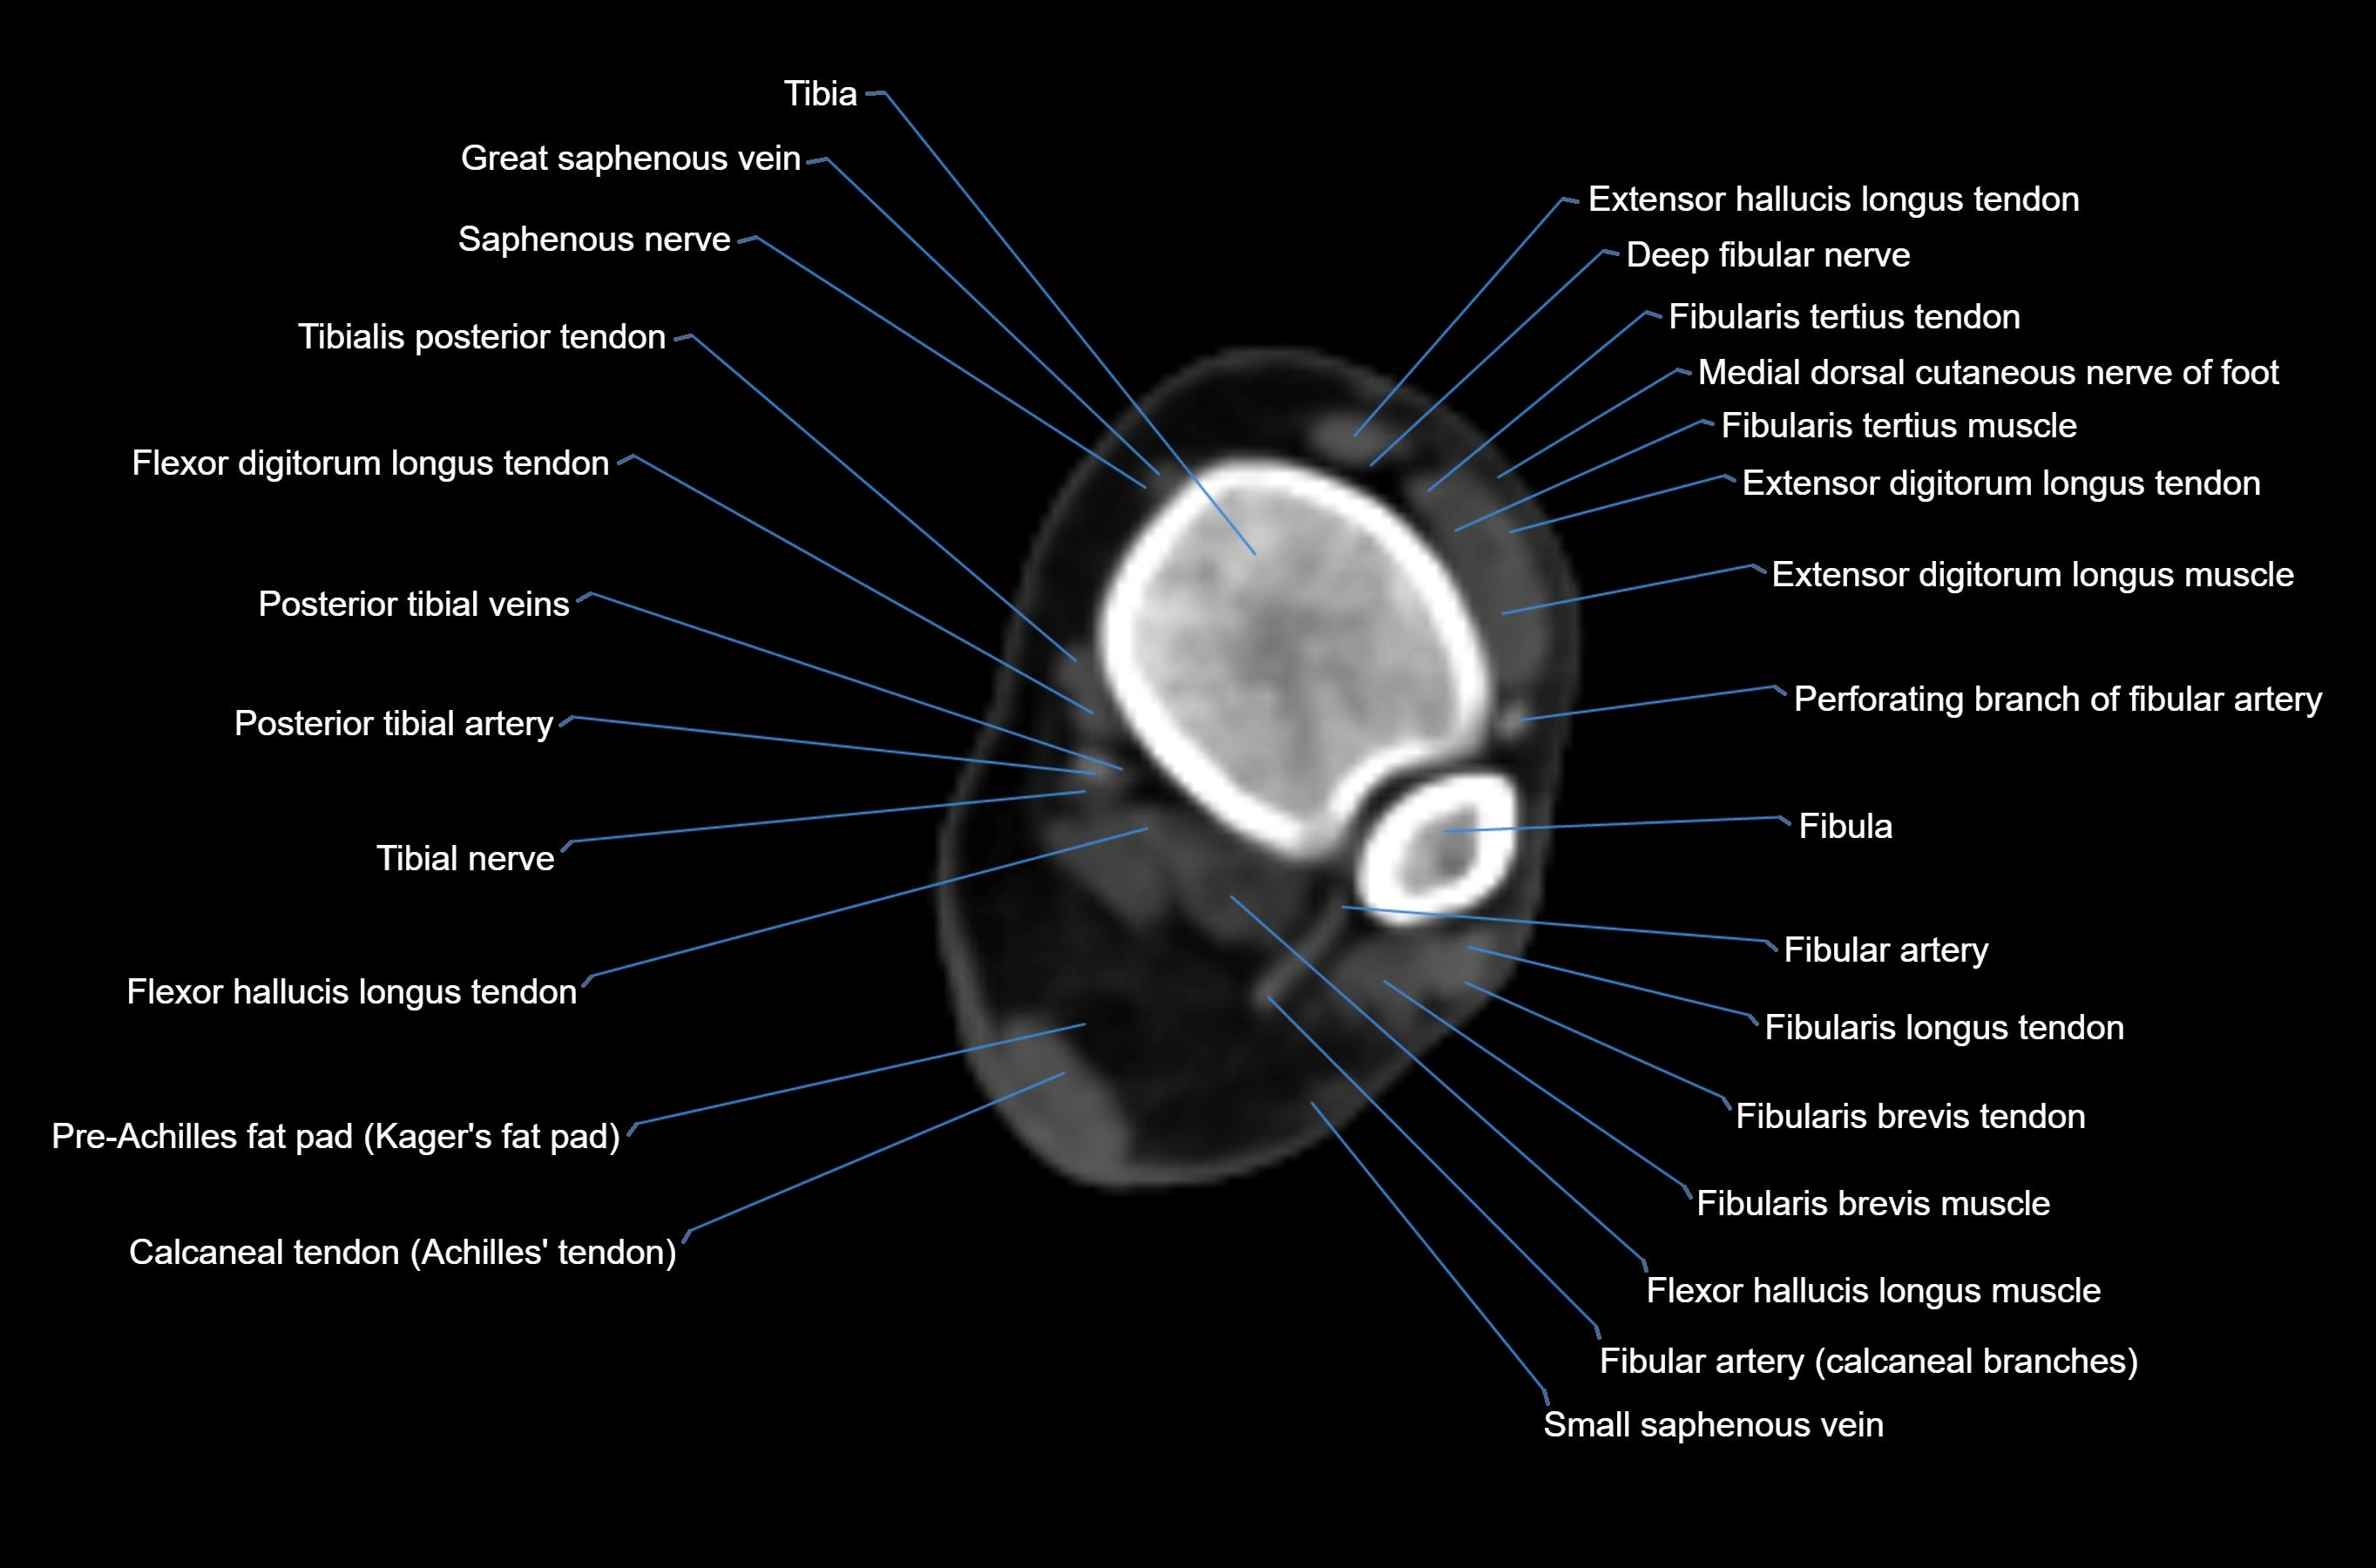

CT image